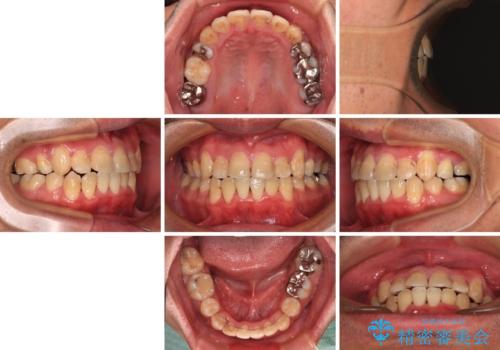

- 上下の八重歯やデコボコを気にして来院された患者様です。

上下ともに八重歯が顕著であったので、上下左右第一小臼歯4本を抜歯し、ワイヤー装置にて矯正治療を行うこととしました。

デコボコを治したい 八重歯の抜歯矯正